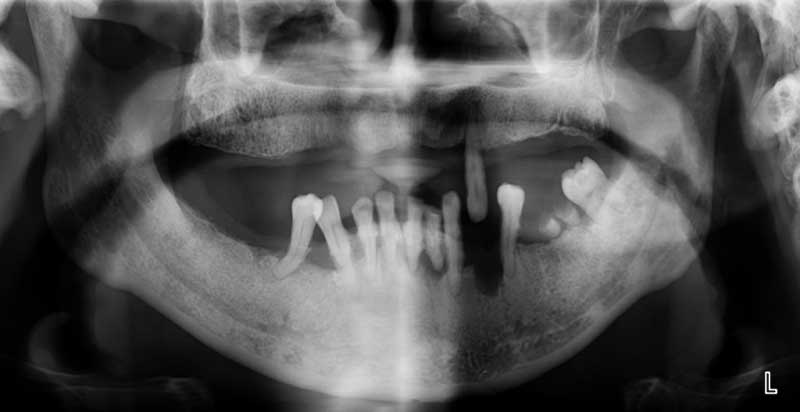

全口重建最初步就是做詳細的口腔檢查,在精密儀器輔助下為患者做出精確的診斷。之後幫患者擬出多套的治療計劃,提供患者參考,再從中選出最適合患者的治療計劃,專為患者良身打造。

全口重建是個龐大的跨科治療療程,前置作業通常包括洗牙,或是拔除無法救治的牙齒,還有根管治療、補牙、牙周病治療等,另還有其它口腔整理工作。

而一部份患者仍需配合局部或是全口的矯正重整,再使用傳統的活動假牙、固定假牙或目前最盛行的全口植牙來搭配全口的重建療程。

案例1